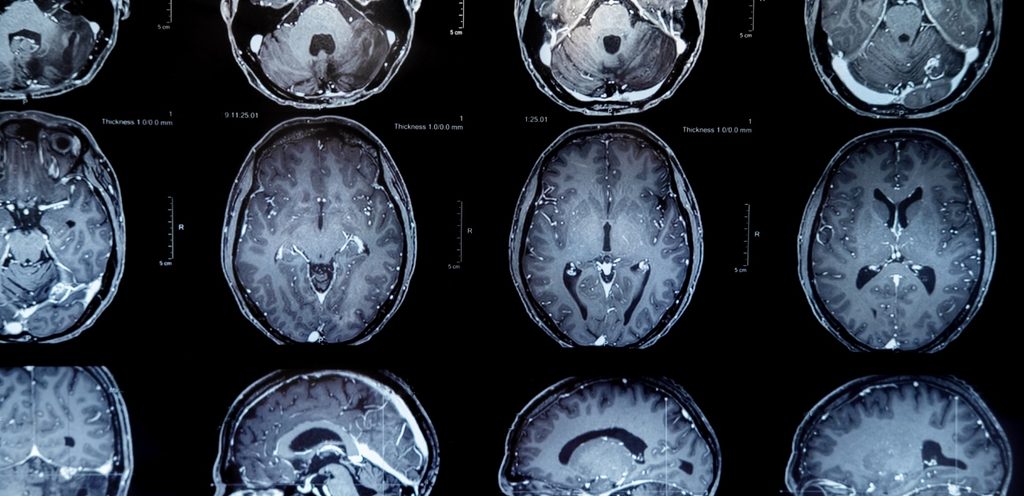

الورم السحائي هو من أكثر أنواع الأورام شيوعًا التي تتكون في الرأس، ينشأ وينمو ببطء في الأغشية الواقية المحيطة بالدماغ والحبل الشوكي. يسبب هذا الورم ضغطًا على الأجزاء المجاورة بالدماغ والأعصاب والأوعية الدموية. واقرأي هنا أهم التوصيات الجديدة للكشف المبكر عن سرطان الثدي

تكمن خطورة الورم السحائي بحيث أنه ينمو ببطء شديد على مدى عدة سنوات من دون أن يسبب أي عوارض تذكر، ولكن آثاره الجانبية تكمن فيما بعد بتأثيرها على أنسجة المخ، والأعصاب والأوعية الدموية المجاورة مما يؤدي لحدوث إعاقة خطيرة في بعض الأحيان.